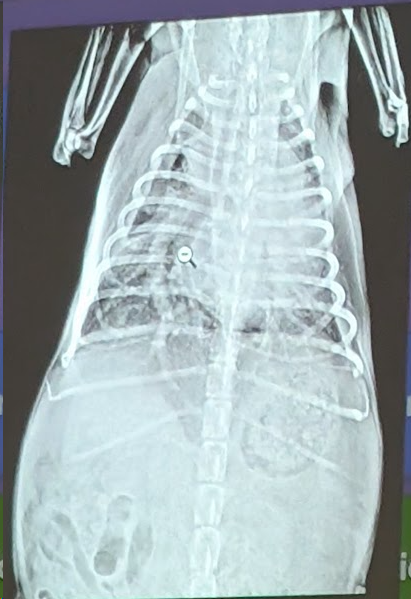

Preguna 1 - Multiple respuesta

- Se trata de un abdomen de gato

- Obstrucción intestinal

- Presenta una dilatación gastrica sin torsión (ya que el fundus y piloro gastrico están en su sitio).